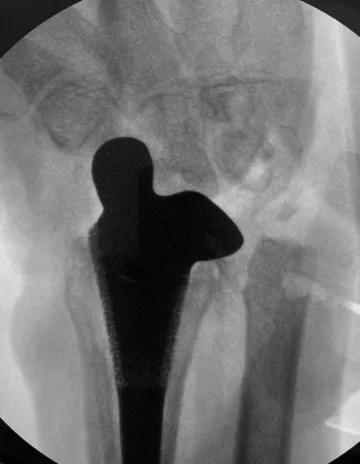

患者手术后x光片